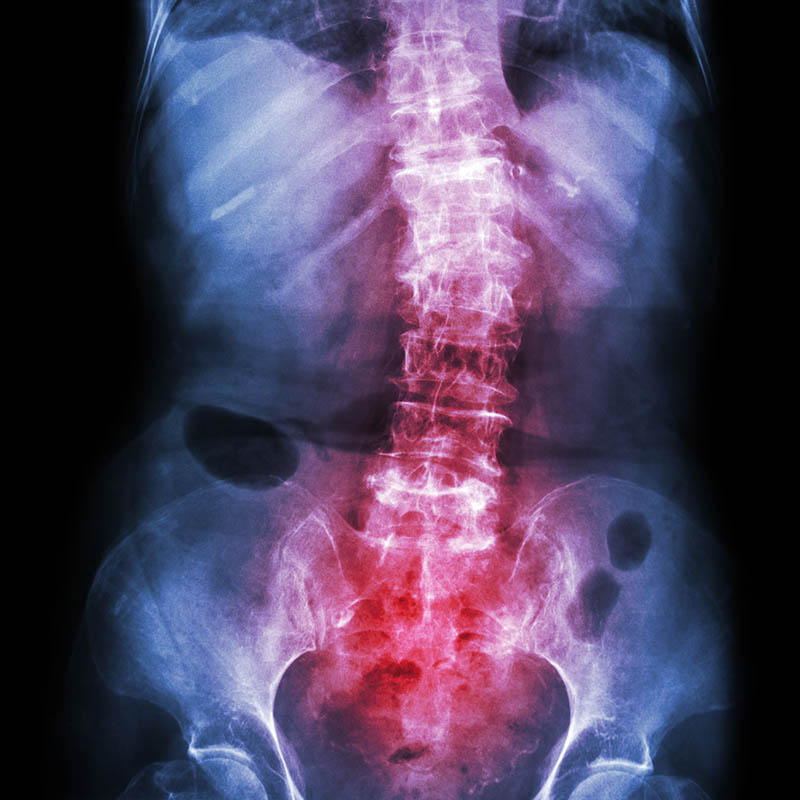

Patients with ankylosing spondylitis display distinct fecal microbiota signature

Patients with ankylosing spondylitis demonstrate a distinct fecal microbiota signature that is linked to levels of fecal calprotectin, but not other clinical parameters, according to data published in Arthritis Research & Therapy.